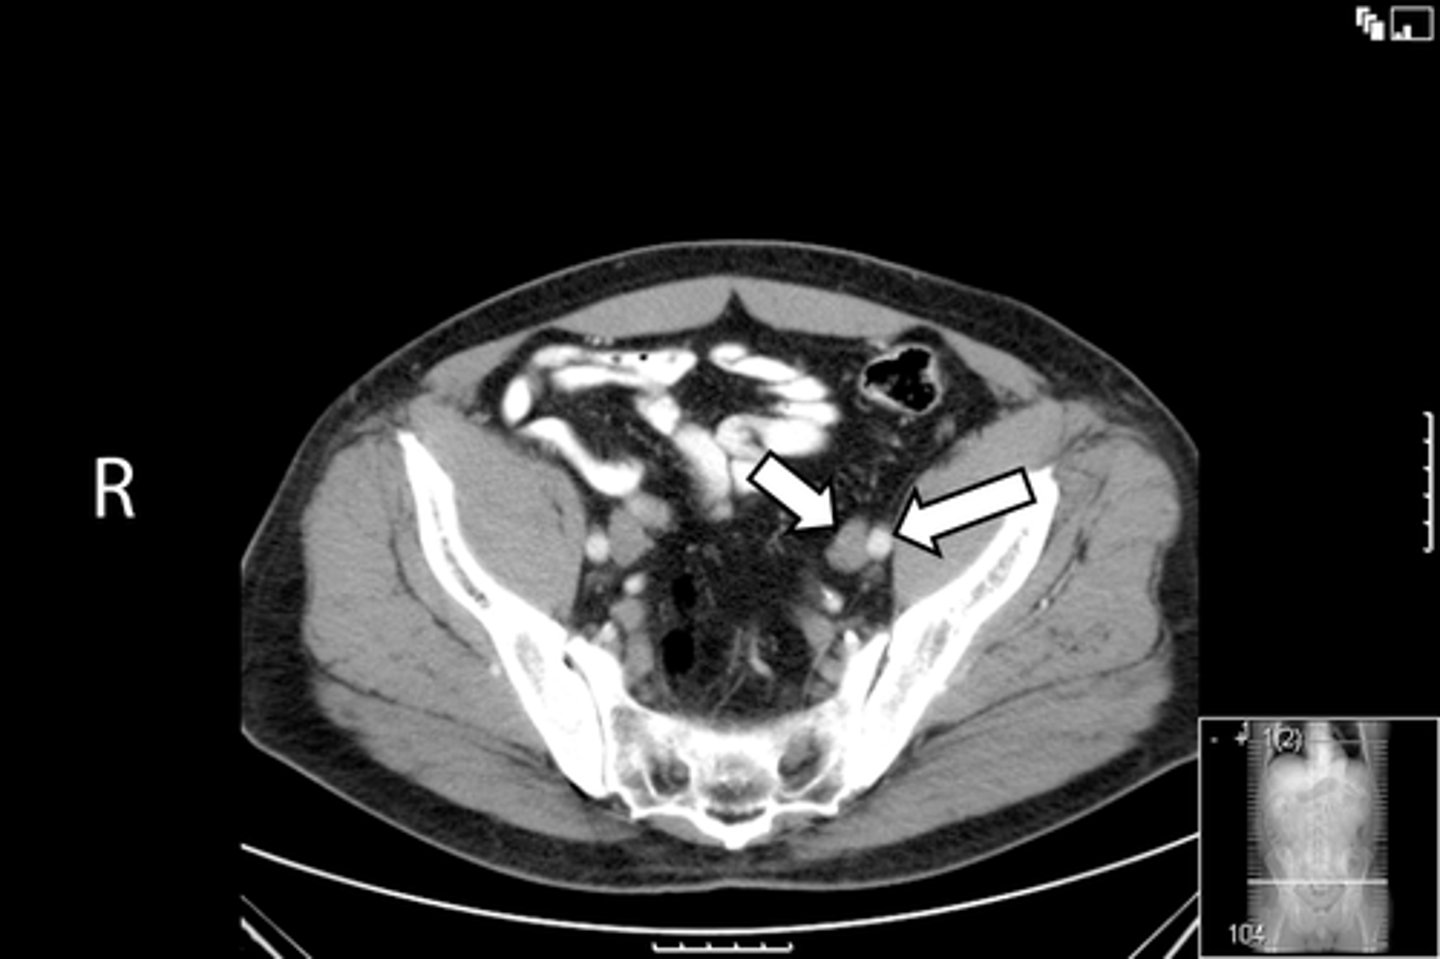

Obturator foramen

What is indicated in the image?

<p>What is indicated in the image?</p>

12

New cards

Pubic symphysis

13

Sacroiliac joint

14